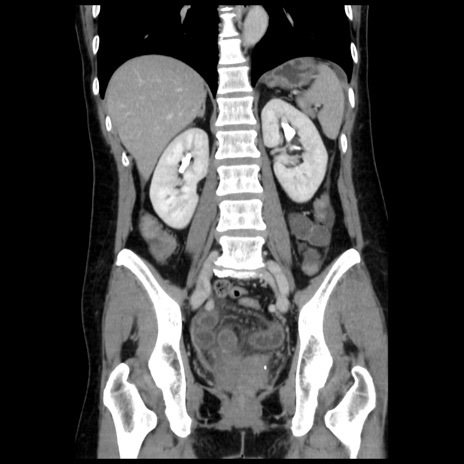

症例10(冠状断像)

【症例】 50歳代女性

【主訴】 腹痛

【現病歴】前日生レバーを食べた。今朝に排便あり。 昼前に突然発症の腹痛を生じ、当院救急外来を受診した。

【既往歴】 子宮筋腫にてで子宮全摘後

【身体所見】 意識清明、腹部:平坦、軟、下腹部やや左を中心に圧痛・反跳痛あり、筋性防御あり

【データ】WBC 7800、CRP 0.07